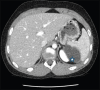

Epidermoid splenic cyst is a rare benign tumour in children, accounting for 10% of all cystic lesions of the spleen and is the most common diagnosis of non-parasitic splenic cysts. Its discovery could be incidental or happen after an imaging workup for a mass or abdominal pain. Since total splenectomy exposes a patient to the occurrence of overwhelming post-splenectomy infection, laparoscopic partial splenectomy has been increasingly popular over the past two decades because it preserves the immune function of the spleen. This technique should only be performed by a well-trained team because of the high risk of bleeding. The authors report the cases of three patients who underwent laparoscopic partial splenectomy: a 7-year-old girl with no relevant history with a 4.5-cm epidermoid cyst involving the lower pole of the spleen, a 13-year-old boy, type 1 diabetic on insulin therapy, with a 7-cm epidermoid cyst of the upper pole of the spleen and a 14-year-old girl, with no previous history, with a 6-cm upper pole epidermoid splenic cyst. Operating times were 2 h 30 min, 3 h and 4 h 30 min, respectively. The intraoperative blood loss was 100 mL, 350 mL and 300 mL, respectively. The length of hospital stay was 6 days for each patient. No blood transfusion was performed perioperatively. With a mean follow-up duration of 21 months (32 months, 21 months and 10 months, respectively), no complication or recurrence occurred.